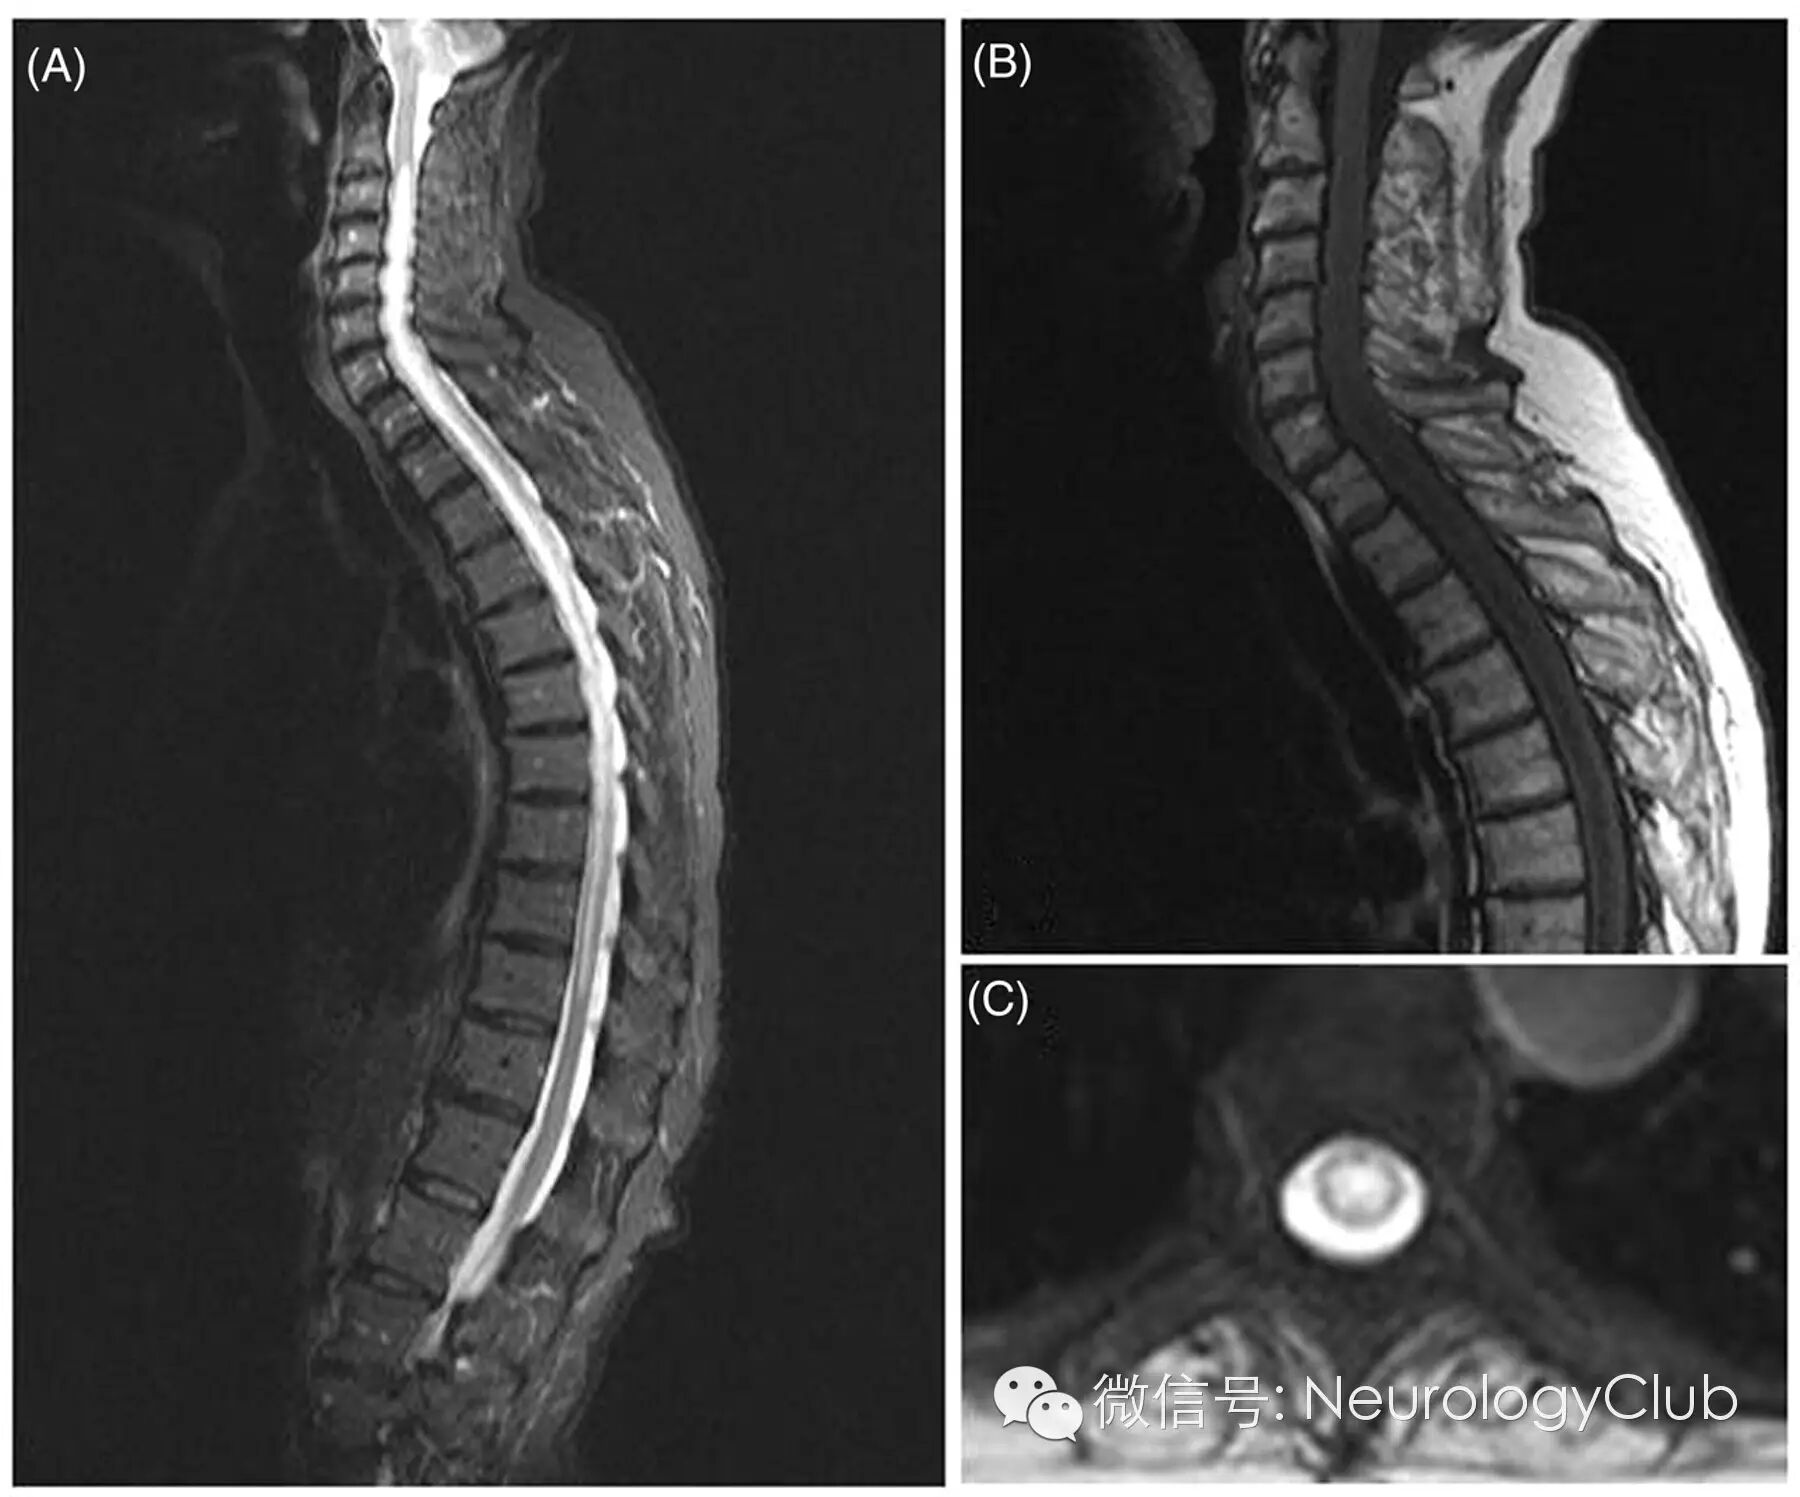

1视神经脊髓炎

(AQP4阳性的NMO患者。A-B:C2-T10可见长节段脊髓病灶,脊髓中央水肿,呈T2WI高信号,T1WI低信号;C:横断面T2WI脊髓周围白质未受累)